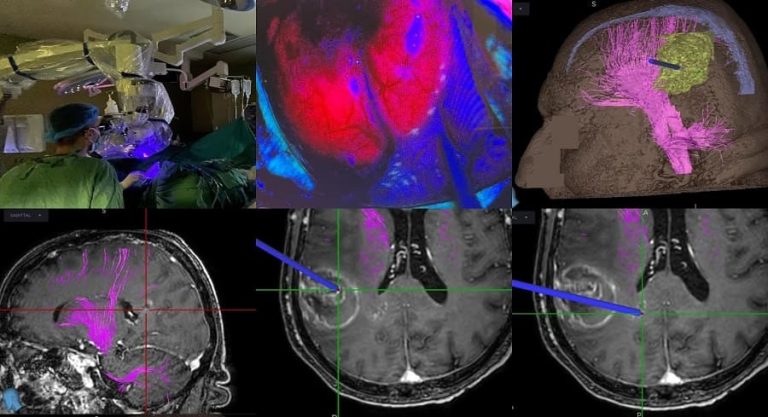

Πρωτοποριακή επέμβαση σε δημόσιο νοσοκομείο με χρήση 5-αμινολεβουλινικού οξέος (5-ALA) για την χειρουργική εξαίρεση κακοήθους όγκου εγκεφάλου πραγματοποιήθηκε με απόλυτη